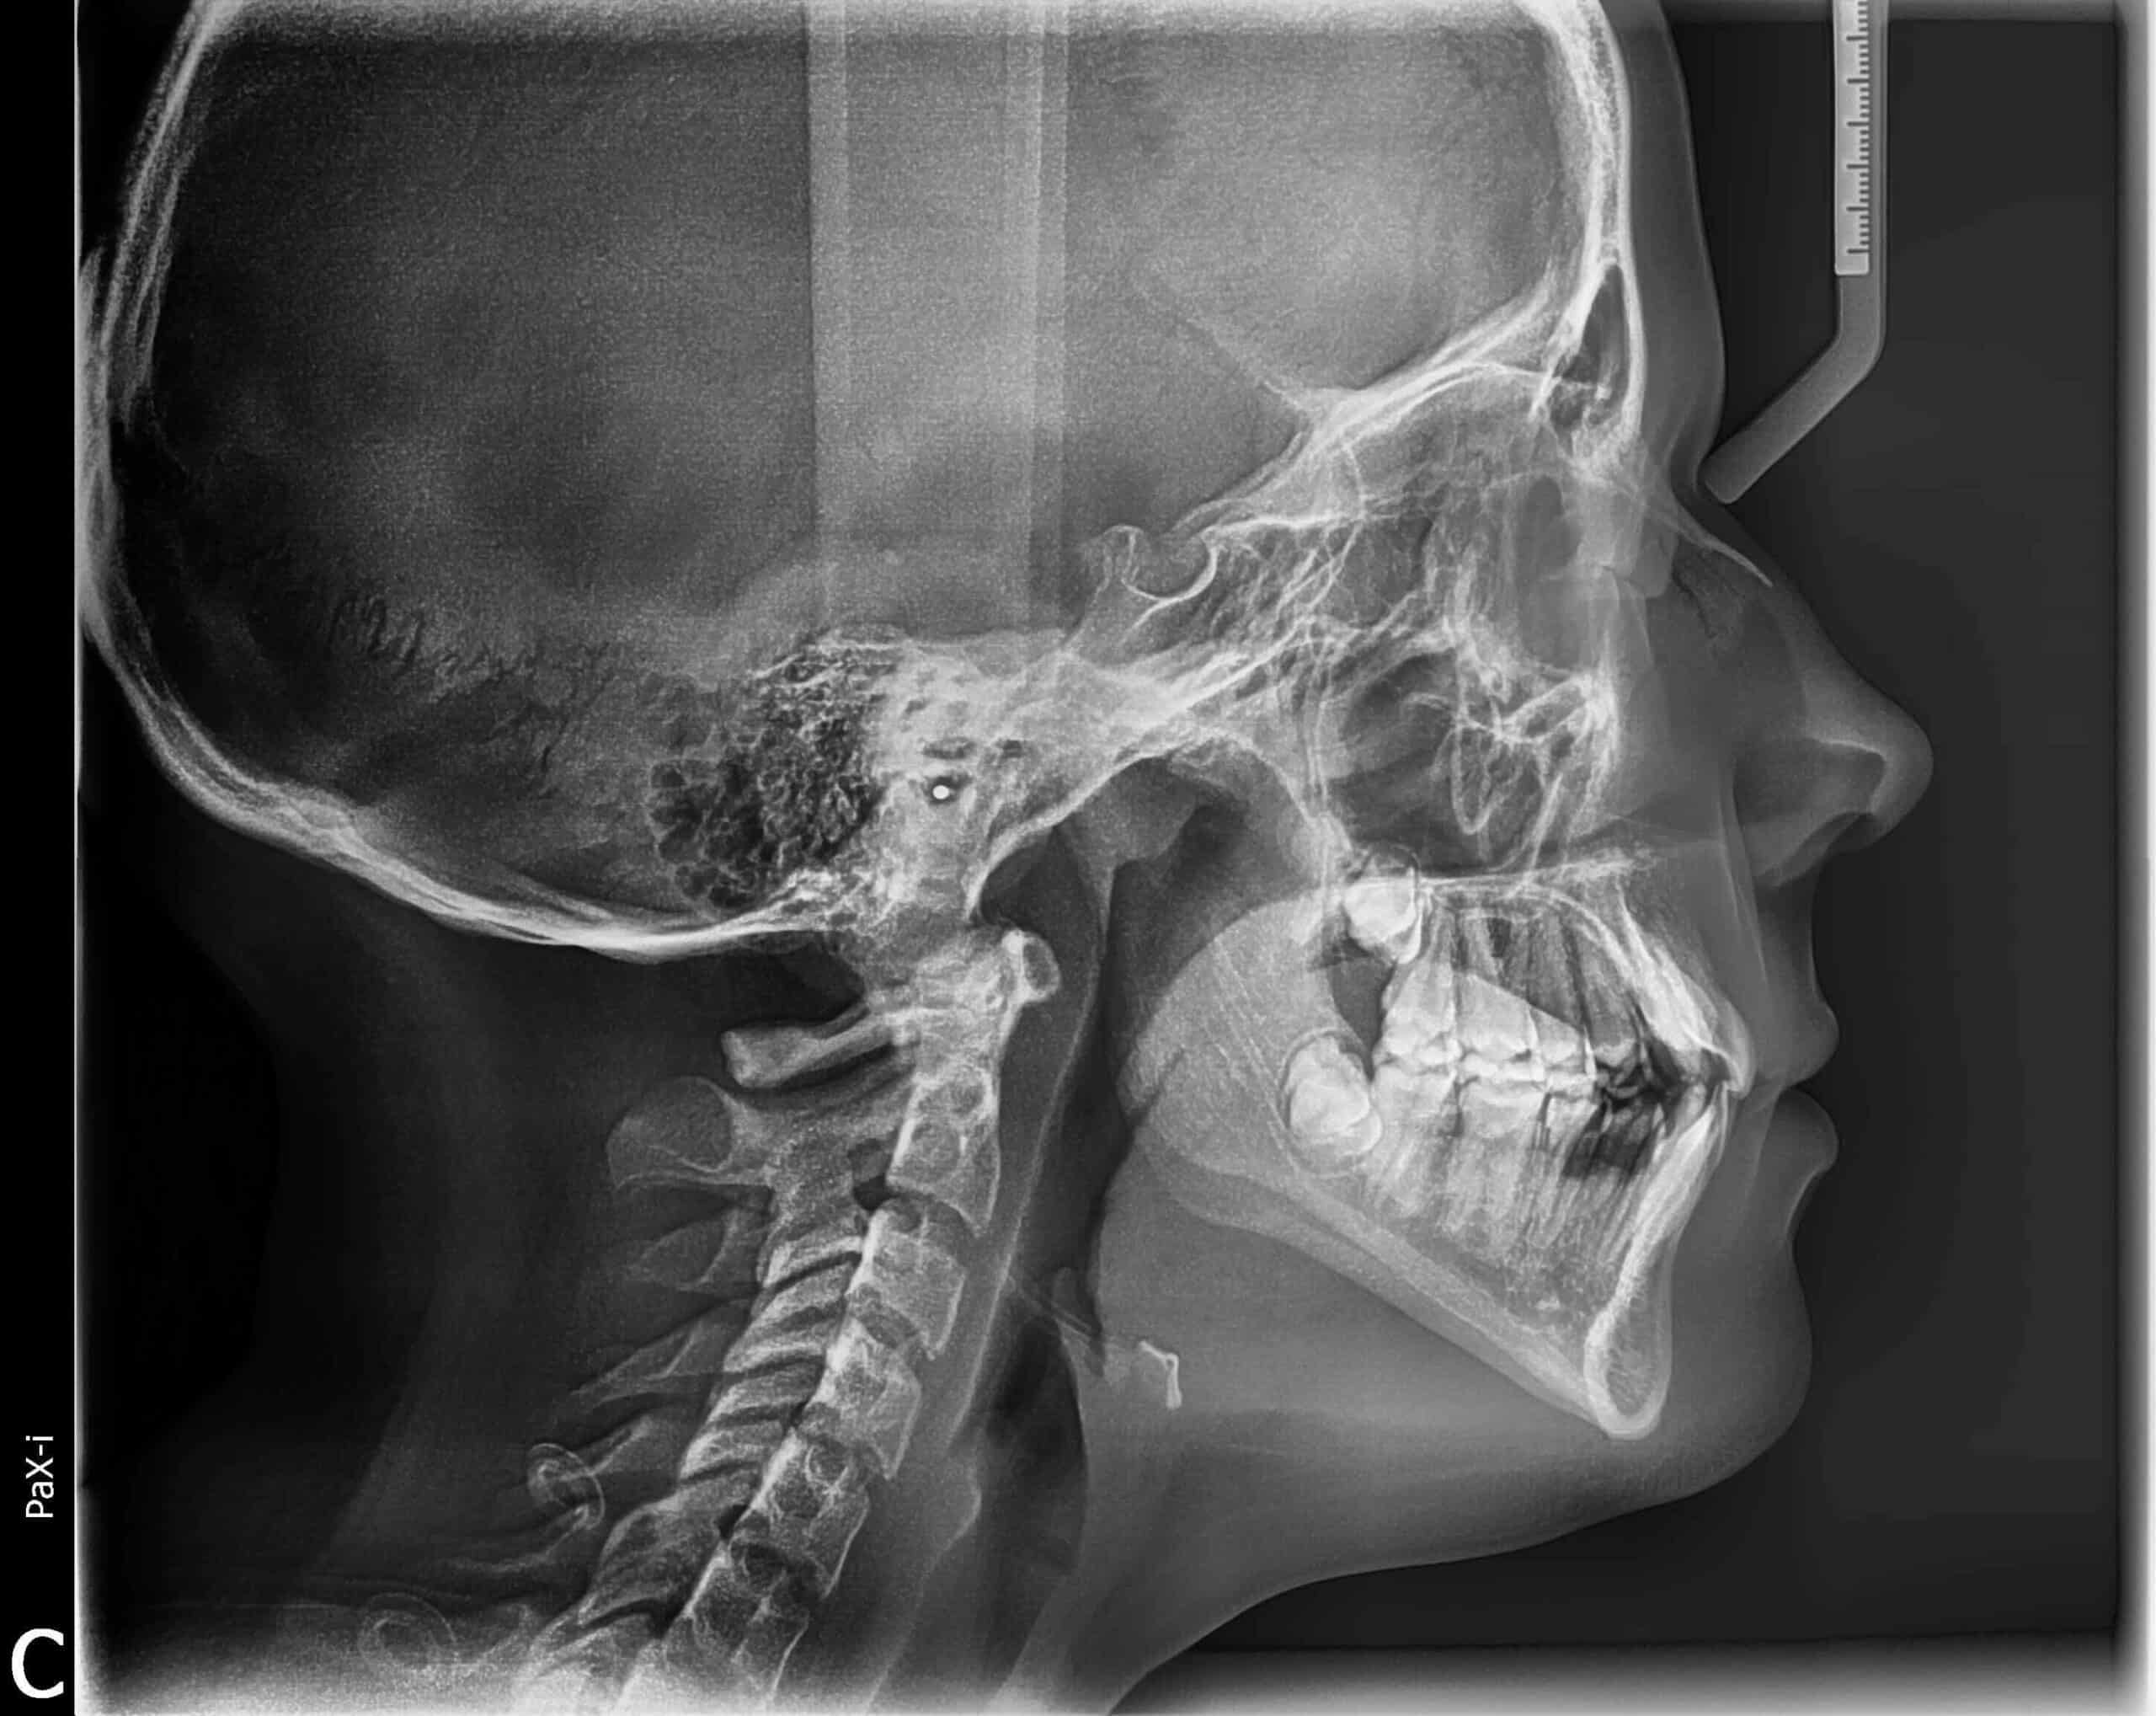

Case Study: Overcrowding & Misaligned Teeth Treatment

Creating Healthy, Balanced Smiles with Expert Orthodontic Care

Overcrowding and misaligned teeth can affect both the appearance of your smile and your overall oral health. At Smiles Orthodontics, we use modern orthodontic solutions to gently guide teeth into proper alignment. Correcting crowding not only improves the look of your smile but also makes it easier to keep your teeth clean and your bite functioning properly.